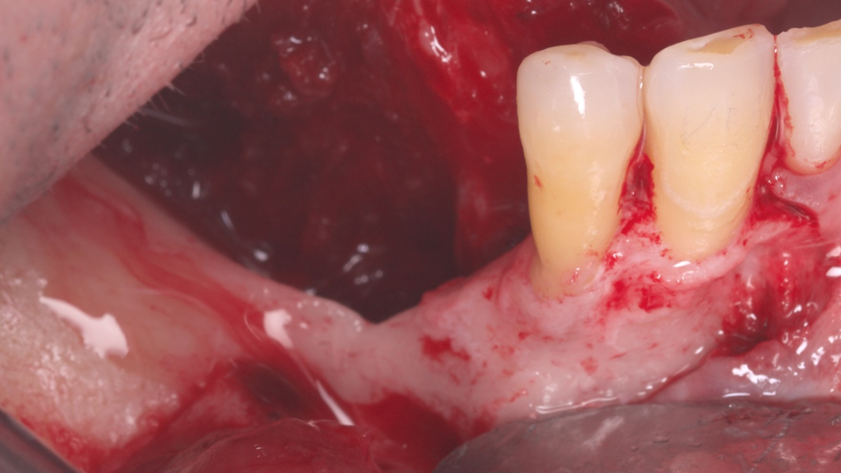

Homem de 60 anos foi encaminhado para reabilitação implantossuportada na região molar inferior direita (Figura 1). O volume ósseo remanescente tridimensional foi acessado por meio de tomografia computadorizada. Revelou uma deficiência vertical de modo que um aumento vertical foi planejado antes da colocação do implante. Seu histórico médico foi verificado e não foram encontradas comorbidades nem condições alérgicas. Não houve achados clínicos intraorais anormais, mas uma deficiência vertical na área molar inferior direita. Nenhum achado anormal foi perceptível no exame extraoral. Um enxerto autógeno em bloco ósseo dividido foi planejado para aumento horizontal e o ramo ipsilateral foi o local doador de escolha. A cirurgia foi realizada sob anestesia local com Articaína 4% e adrenalina 1:100.000. O paciente foi prescrito para enxaguar com Clorexidina 0,12% no pré-operatório, bem como tomar 1mg de Amoxicilina e 8mg de Dexametasona P.O. uma hora antes da cirurgia. Uma incisão mucoperiosteal foi realizada com bisturi número 15C desde o ramo mandibular até a borda mesiovestibular do primeiro pré-molar juntamente com uma incisão perpendicular obliquamente no vestíbulo mandibular. Após o descolamento da mucosa vestibular e liberação do nervo mentoniano, a mucosa lingual também foi descolada (Figura 2). Duas osteotomias verticais e uma horizontal foram realizadas no ramo mandibular com broca 701 para retirada do bloco ósseo necessário à reconstrução horizontal (Figura 3). Após a retirada do enxerto com auxílio de um elevador radicular, o bloco foi cortado longitudinalmente em dois pedaços finos com brocas discais e o osso esponjoso foi raspado para que pudesse ser utilizado como osso lascado (Figuras 4 a 8). Os blocos foram fixados na área edêntula. Um bloco foi fixado na face vestibular e o outro na face lingual. Cada um deles foi fixado com dois parafusos de osteossíntese de 1,5 mm e o osso lascado foi inserido no espaço entre eles (Figuras 9 e 10). A ferida foi fechada com fio de polipropileno 5-0, que foi retirado após 15 dias (Figura 11). A cirurgia cicatrizou sem intercorrências e o paciente recebeu prescrição de amoxicilina 500 mg P.O. a cada oito horas durante sete dias e ibuprofeno 600 mg a cada seis horas durante cinco dias.